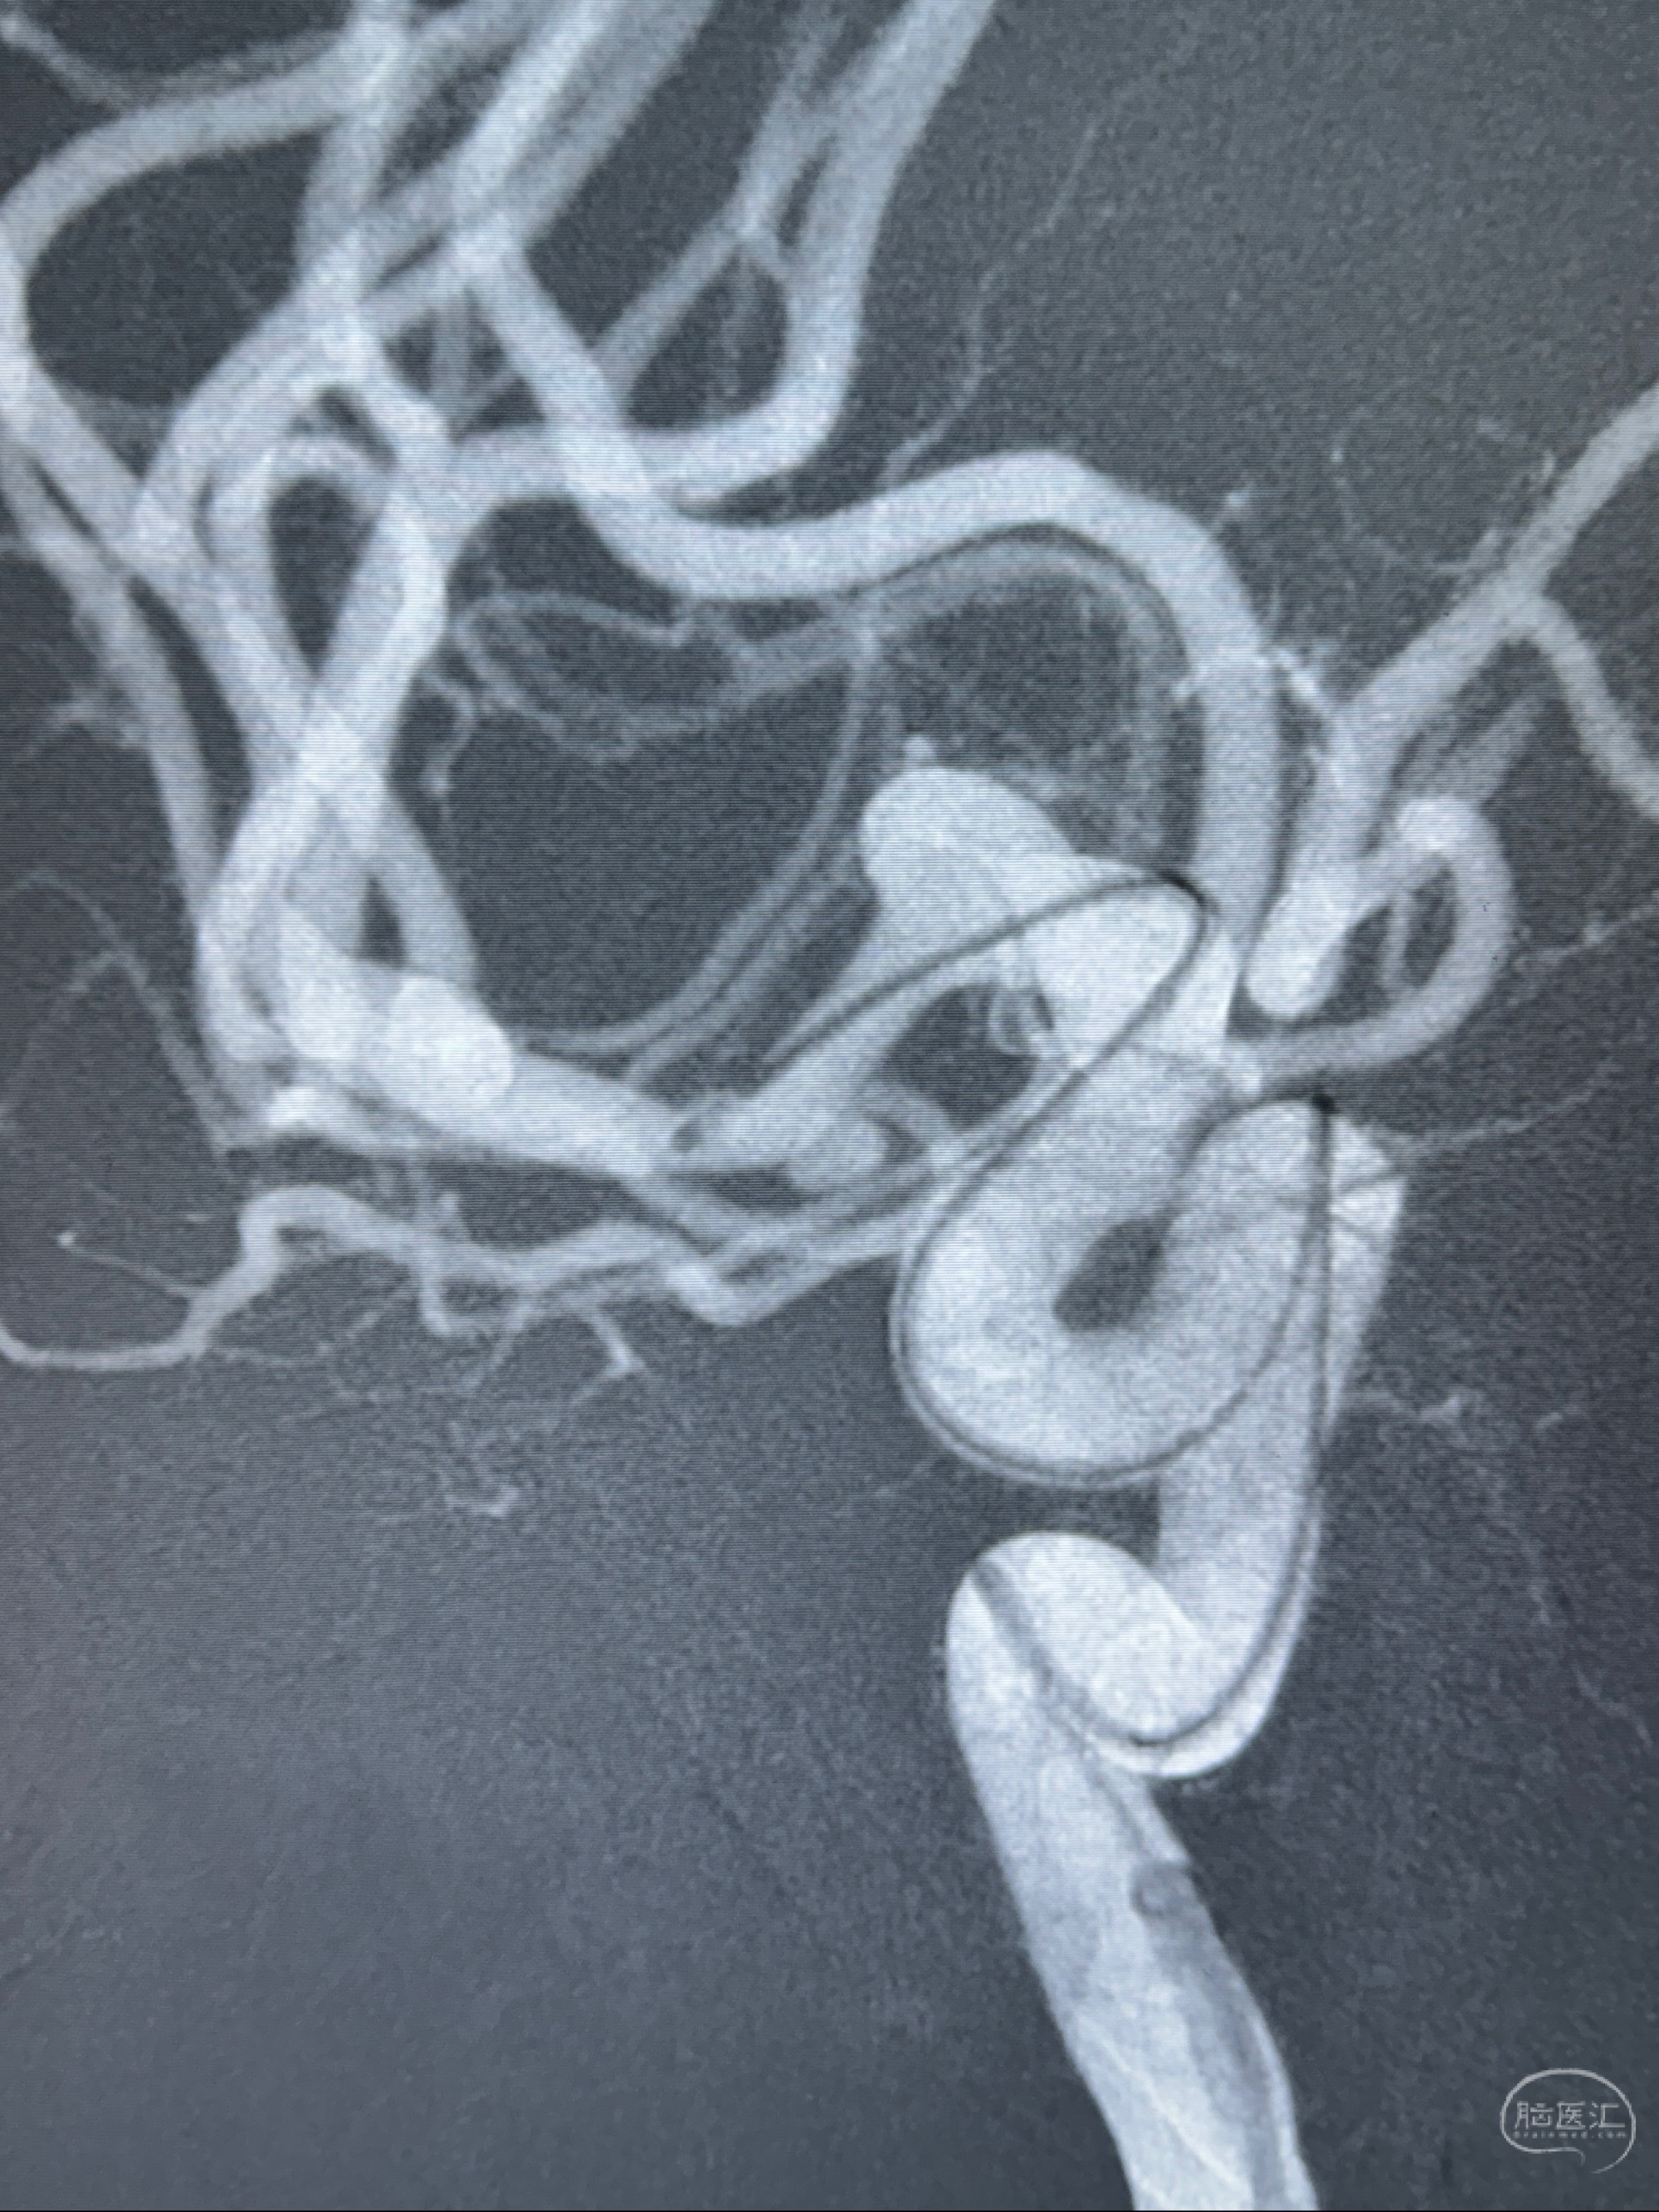

2023-12-04全麻下行支架辅助治疗

S-AB4-20mm

麻醉苏醒佳,遵嘱动作